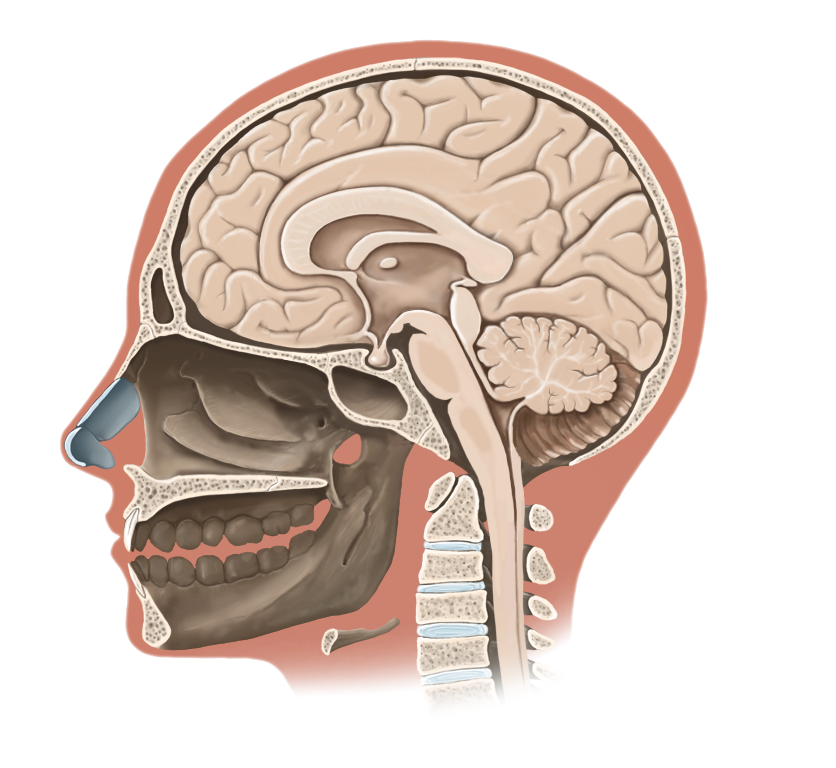

Medical Illustration

All images are works made for hire and are the exclusive property of the client. These are shown as sample purposes of my work only. For licensable work, please see my Illustration Services page.

Medical Illustrator for Precision Graphics, Lachina, and Human Kinetics Publishing (current)

Contract freelancer for many others, some examples of my work below.